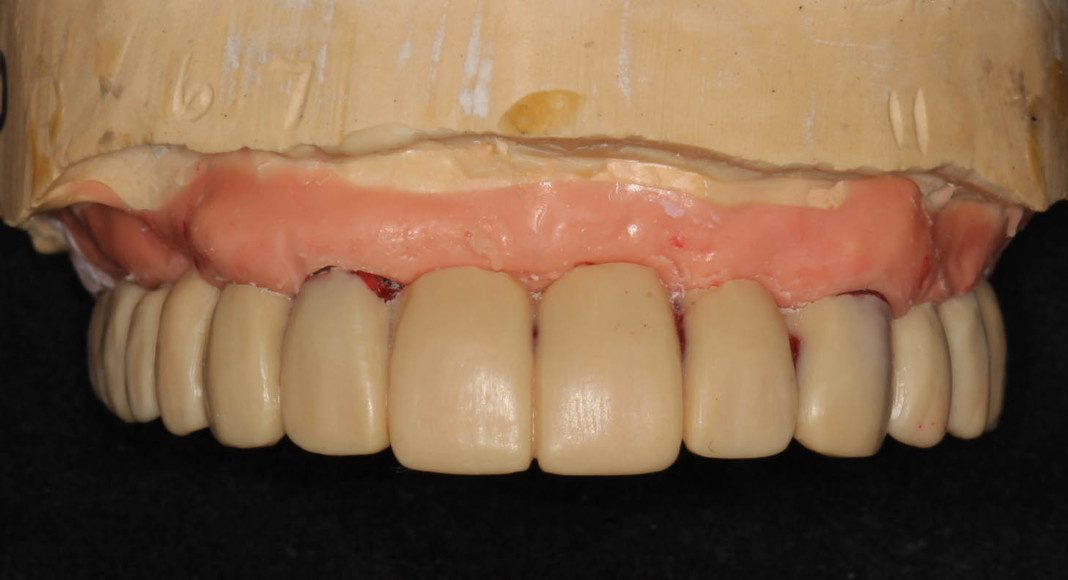

Occlusal view of the wax prototype. This will serve as a template for us to evaluate the tooth length, size and shape. I work with the patient to assure it’s correct before we convert to zirconia.

Frontal view of wax prototype in the patient’s mouth. In her case, we agreed that the teeth were too long. The laboratory then modifies the wax-up to shorten the teeth. 50% of the time we try the modified temporary in. When changes are small, we can advise the lab and they make those changes before converting to zirconia. When changes are many, or the patient wants to see them again, a second wax prototype is tried in for approval.